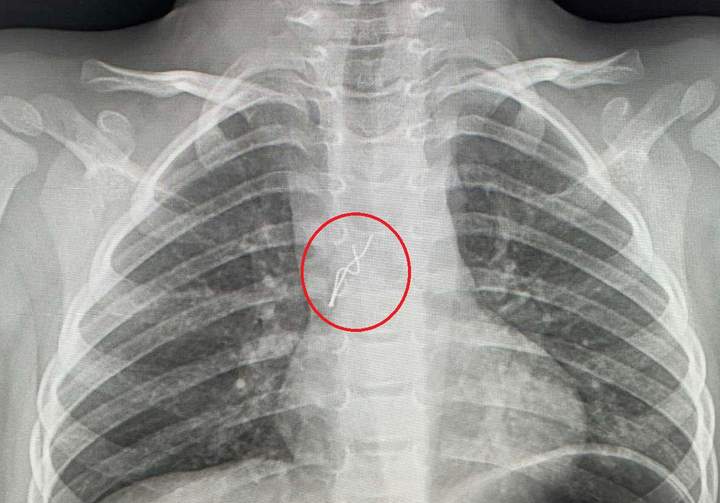

Маленькому пацієнтові відразу зробили рентген. На знімку дитячі хірурги побачили стороннє тіло, гострі краї якого вже встигли травмувати слизову бронха. Хлопчика відразу взяли в операційну.

«Гострими, направленими в різні сторони вусиками, лампочка «дивилася» на мене, – розповів торакальний хірург Олександр Колодій. – Вусики під час дихання травмували слизову оболонку в ділянці біфуркації трахеї, там уже утворилися дрібні крововиливи. Я захопив вусики щипцями і завів їх у тубус бронхоскопа, щоб під час видалення не травмувати ними бронхи і трахею. Разом з тубусом дістав лампочку з бронха дитини».